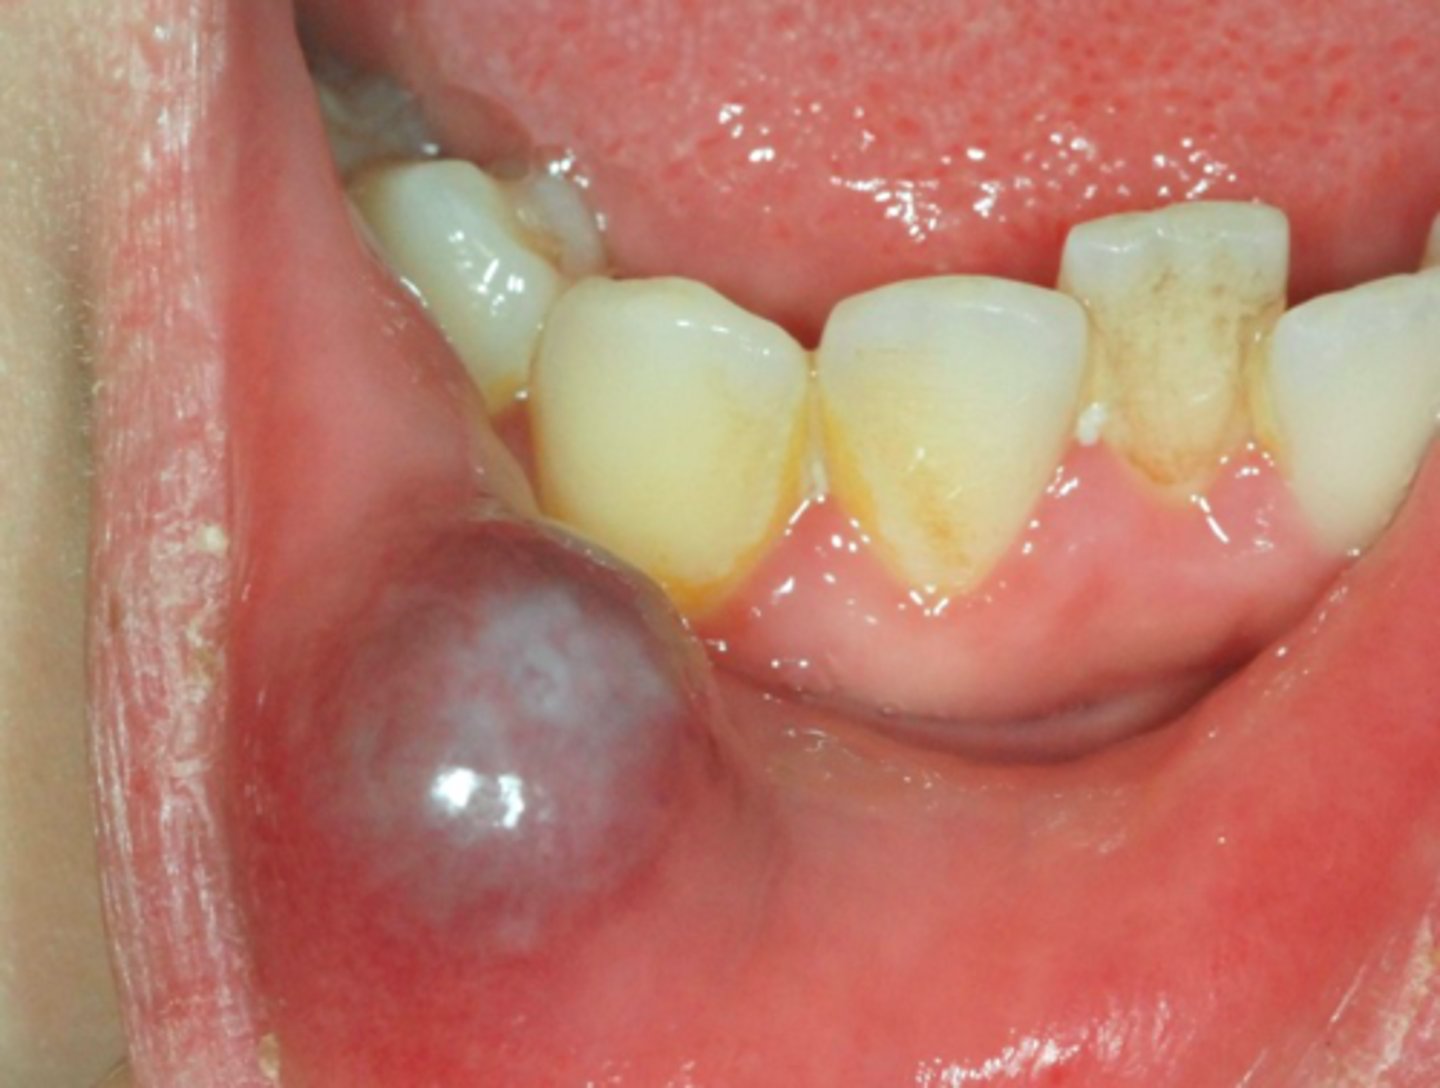

Ranula

A mucocele on floor of mouth is called a ______

sublingual gland

A Ranula is usually associated with what gland?

patient presents with a dome-shaped fluctuant vesicle that looks bluish in color on the floor of the mouth. What is the diagnosis?

floor of mouth

what is the most common location for a Ranula to present?

ID the pathology: